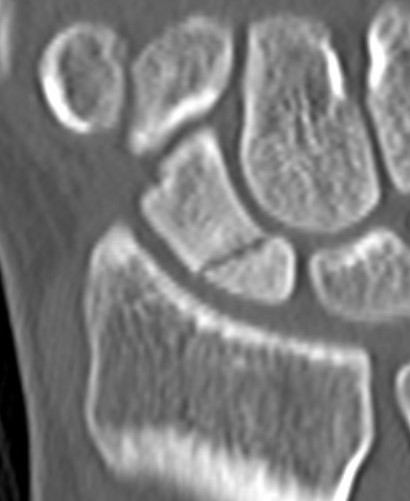

CT

Indication: any potential displacement

Position: patient prone with fully pronated hand over head

Instability

- displacement > 1mm on any film

- intra-scaphoid angle > 35o

- comminution

- proximal pole fractures

- perilunate trans-scaphoid dislocation

Scaphoid waist fracture 1 mm displaced

Scaphoid fracture with significant displacement

Scaphoid proximal pole fracture